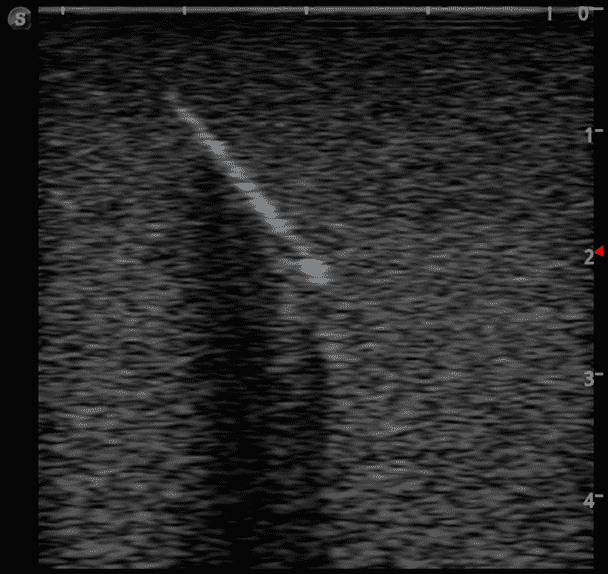

Foreign Body Ultrasound Training Model

This training block is designed for training users in the techniques associated with ultrasound guided foreign body identification, targeting, and retrieval.

· High-quality ultrasound images

· Objects found in the human body including:

Glass shards

Wood splinter

Bullet

Plastic fragments

Metal fragments